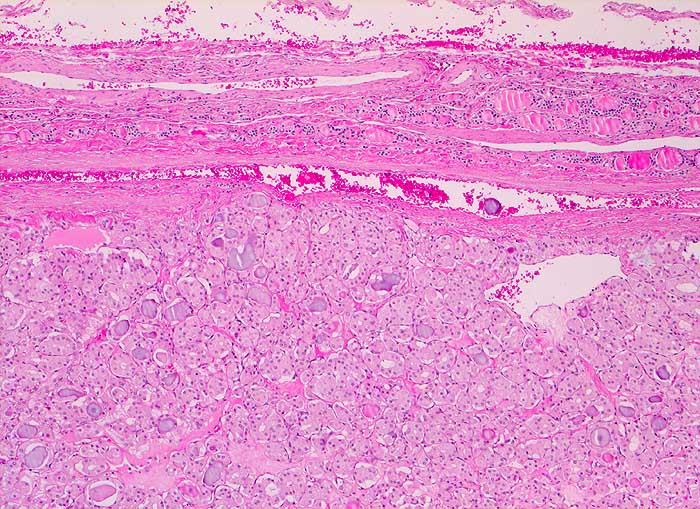

Punktate aus mikrofollikulären oder trabekulären Adenomen sind zellreich und kolloidarm. Die Thyreozyten bilden oft Mikrofollikel oder kleine Rosetten, die eosinophile Kolloidtropfen umschliessen. Die Kerne sind gleichförmig rund, fein granuliert und zeigen keine Atypien. Gelegentlich finden sich regressive Veränderungen. Zytologisch sind follikuläre Adenome und hoch differenzierte follikuläre Karzinome nur schwer zu unterscheiden. Aus diesem Grund werden beide Läsionen mit dem Begriff "follikuläre Neoplasie" bezeichnet. Unten sind zwei Beispiele von mikrofollikulären Adenomen abgebildet.